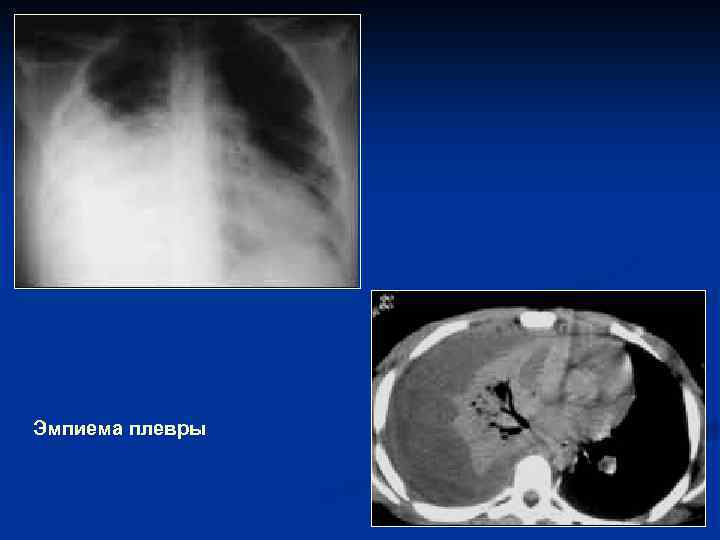

Осложнения пневмоний n n n Экссудативный плеврит Эмпиема плевры Абсцедирование (присоединение гноеродной флоры, нарушение кровообращения и проходимости мелких бронхов, чаще при стафилококковой пневмонии через 5 -7 дней от начала) Сепсис Диафрагматит (утолщение купола, его высокое расположение, нечеткость, неровность контура) Дисковидный коллапс (ателектаз) – рефлекторная реакция на воспаление. Имеет вид тяжа, переходит на соседний сегмент

Эмпиема плевры